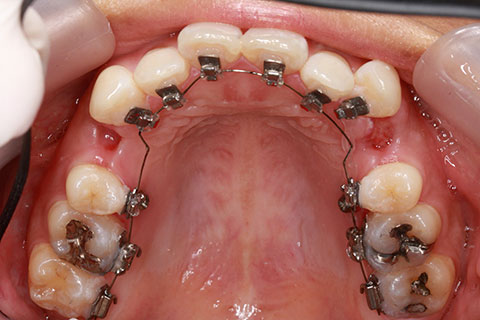

治療中(開始半年後)

治療後